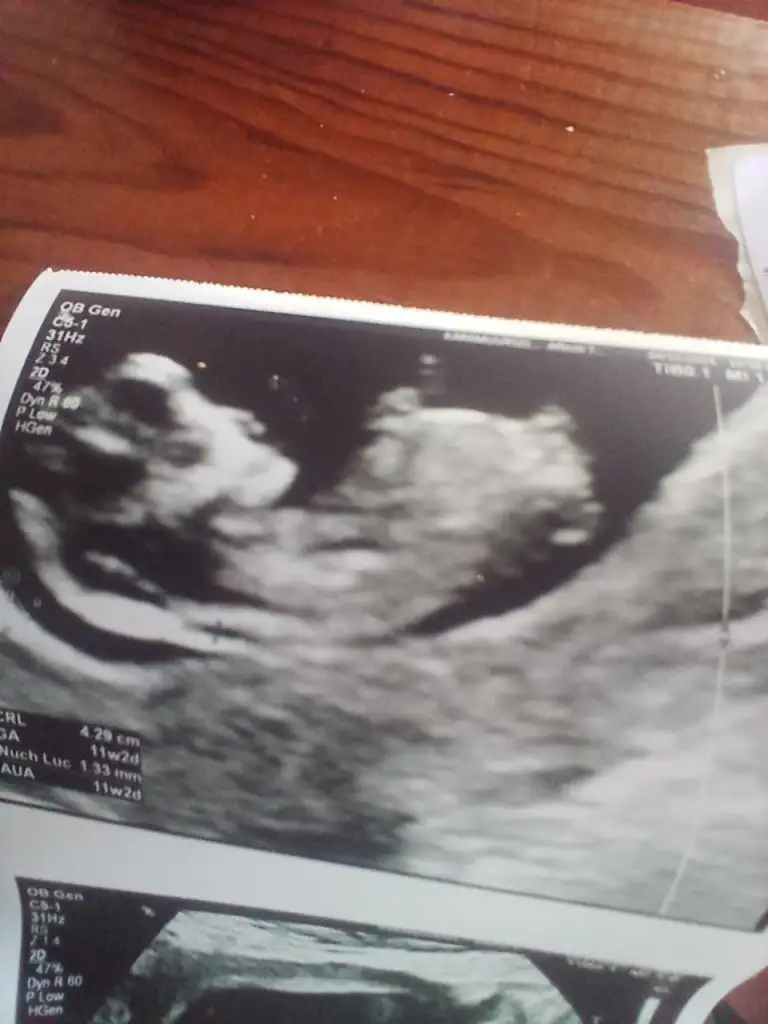

Cinsiyet tahmini yapar mısınız Teyzeler 🌺

Bana da yapabilir misiniz rica etsem 12 haftalık☺️☺️